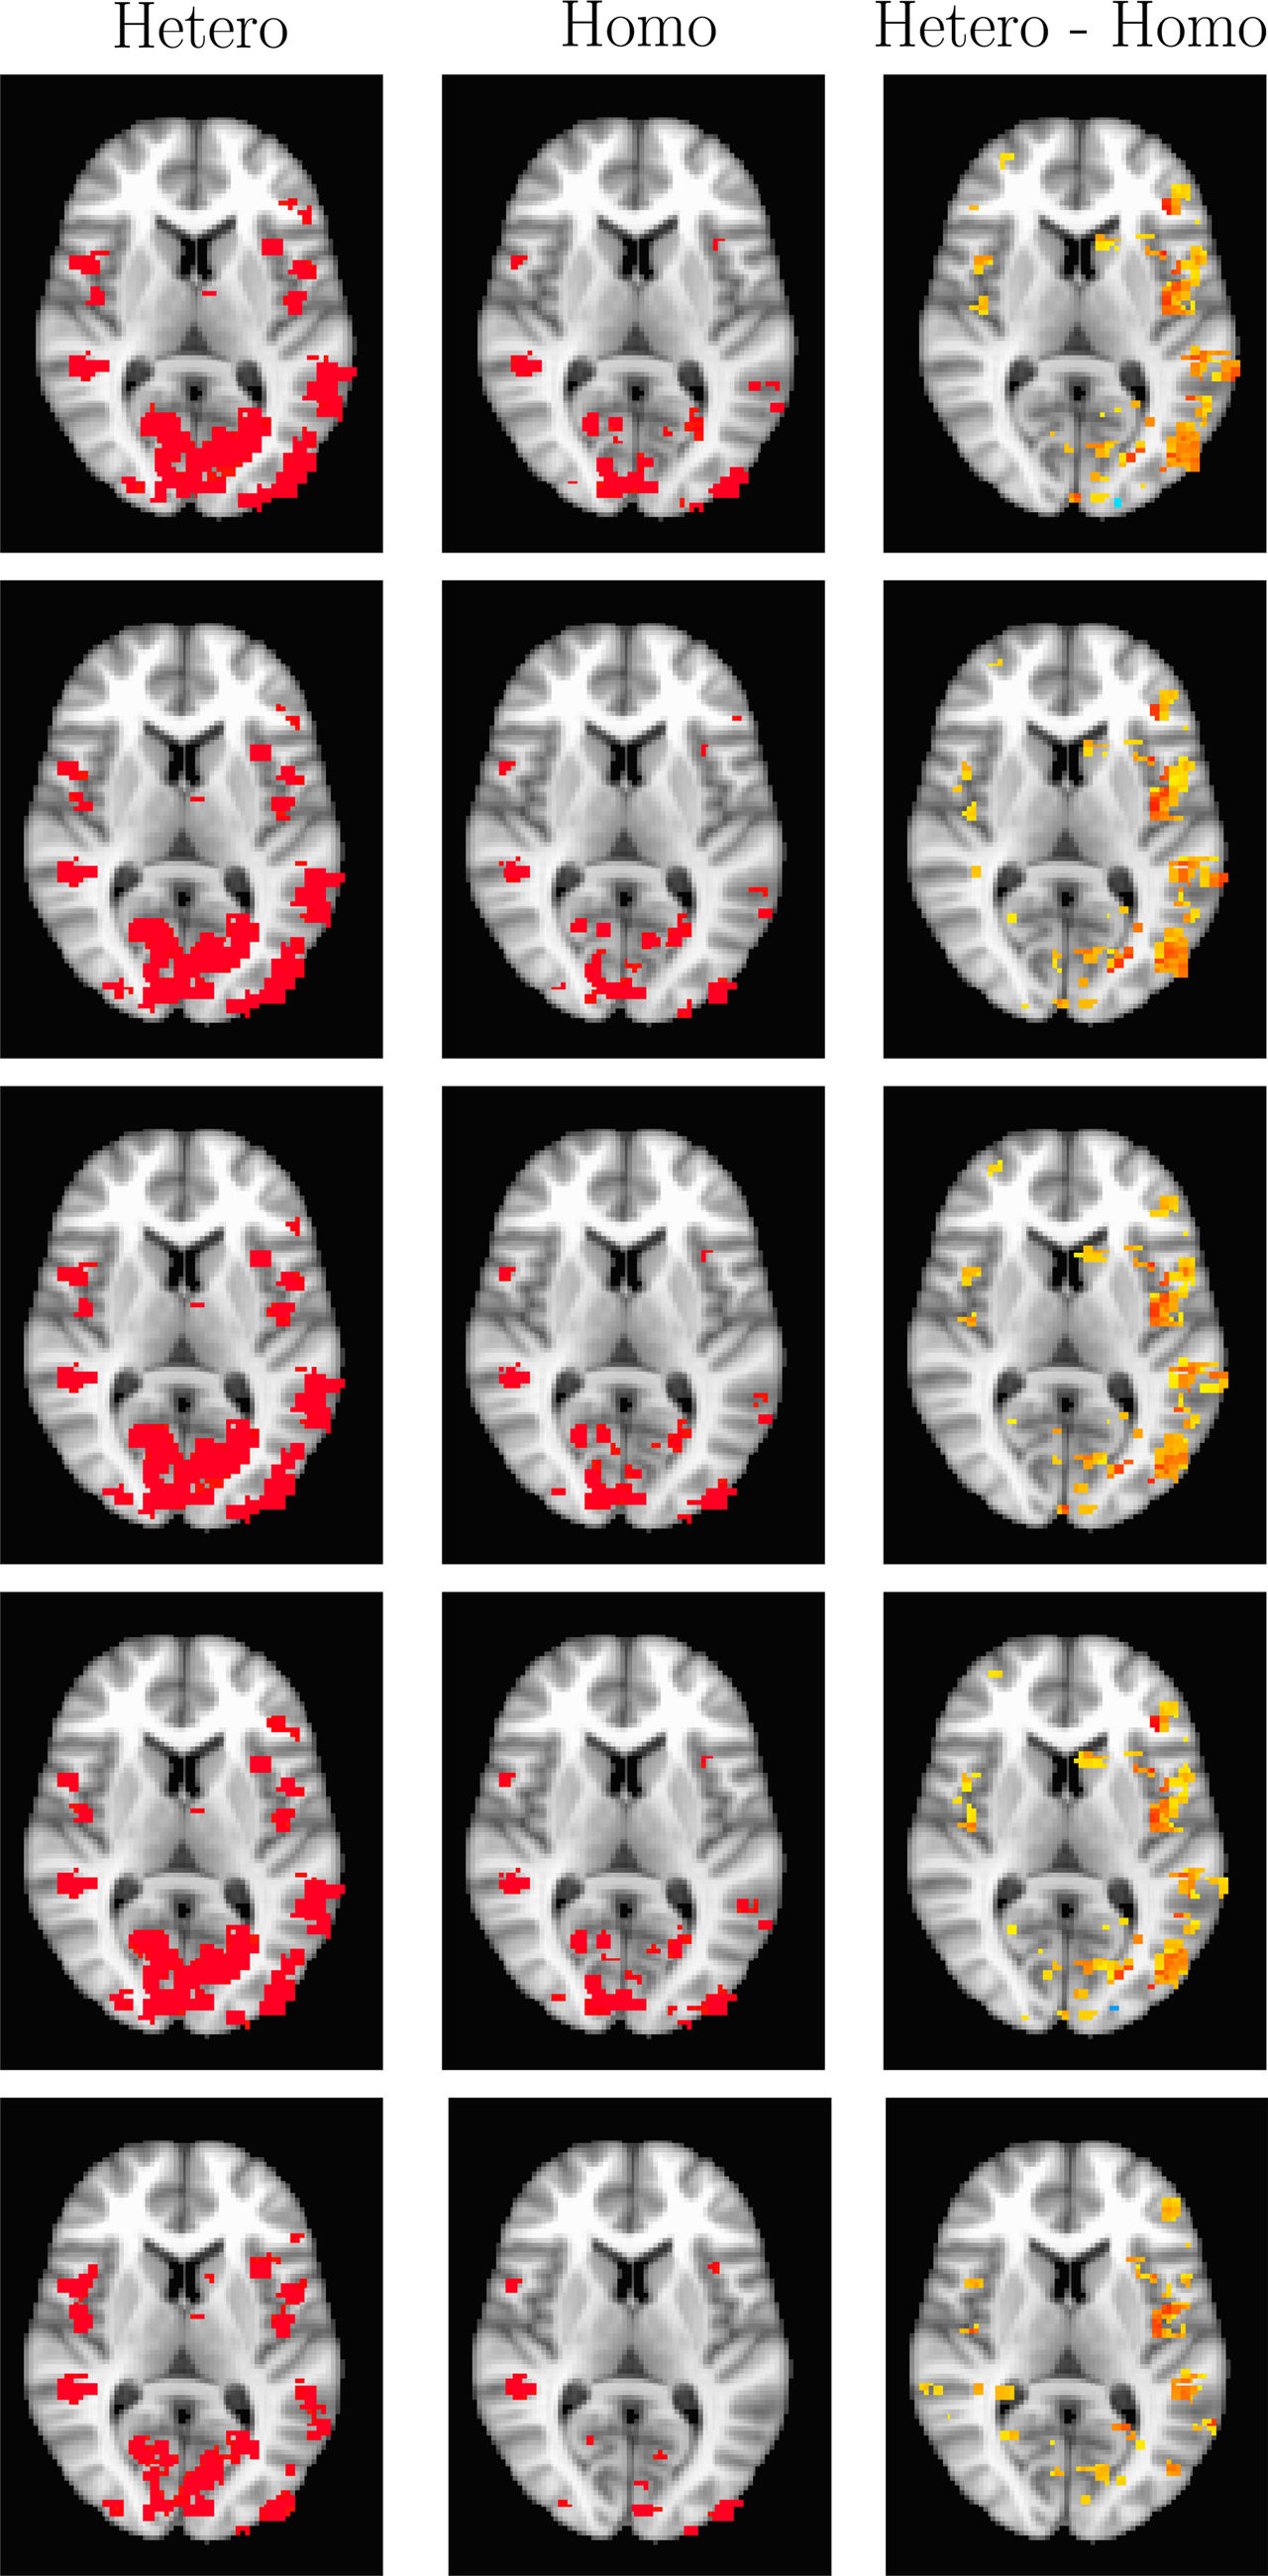

Anders and his colleagues found that the statistical methods traditionally used in analysing fMRI can result in a high level of false positives. The results were published in the scientific journal PNAS and created quite a lot of media attention.

In a follow-up study the research group extended their work and responded to some of the questions and criticism the first article received.

- We previously showed that the non-parametric permutation test can perform better than commonly used parametric tests, as the permutation test is based on a lower number of statistical assumptions.

However, in a few cases even the permutation test produced invalid results.

- We investigated several ways to obtain nominal false positive rates, and finally discovered that physiological noise can disturb the group analyses. To correctly model physiological noise requires monitoring of breathing and pulse during the fMRI experiment, Anders continues.